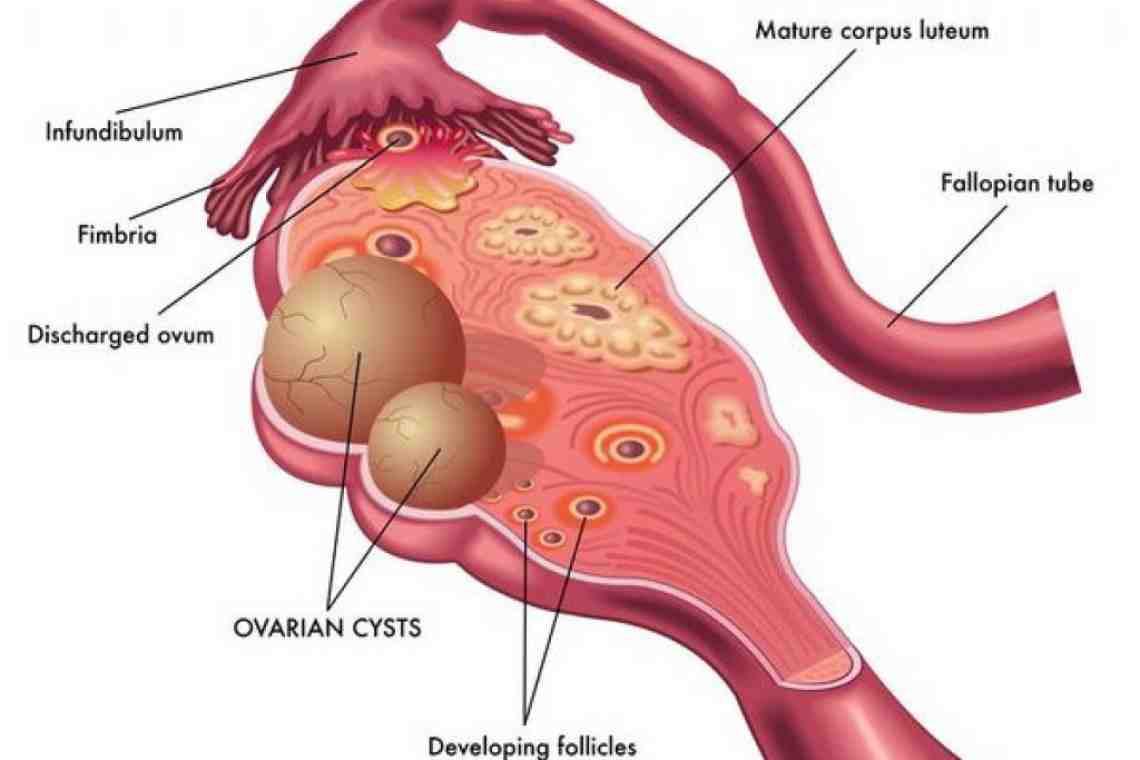

Гистологические изображения фолликулярной кисты яичника